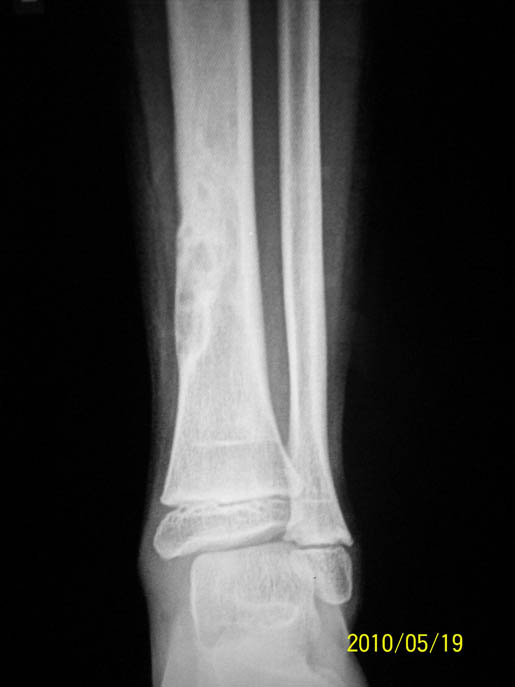

以下是引用随光逐影在2010-5-21 17:25:00的发言:[br]病例1:右胫骨下段非骨化性纤维瘤。[br]病例2:右股骨下段软骨黏液样纤维瘤?非骨化性纤维瘤?

以下是引用流星1234在2010-5-21 14:17:00的发言:[br]1.胫骨非骨化性纤维瘤。2.骨软骨瘤。